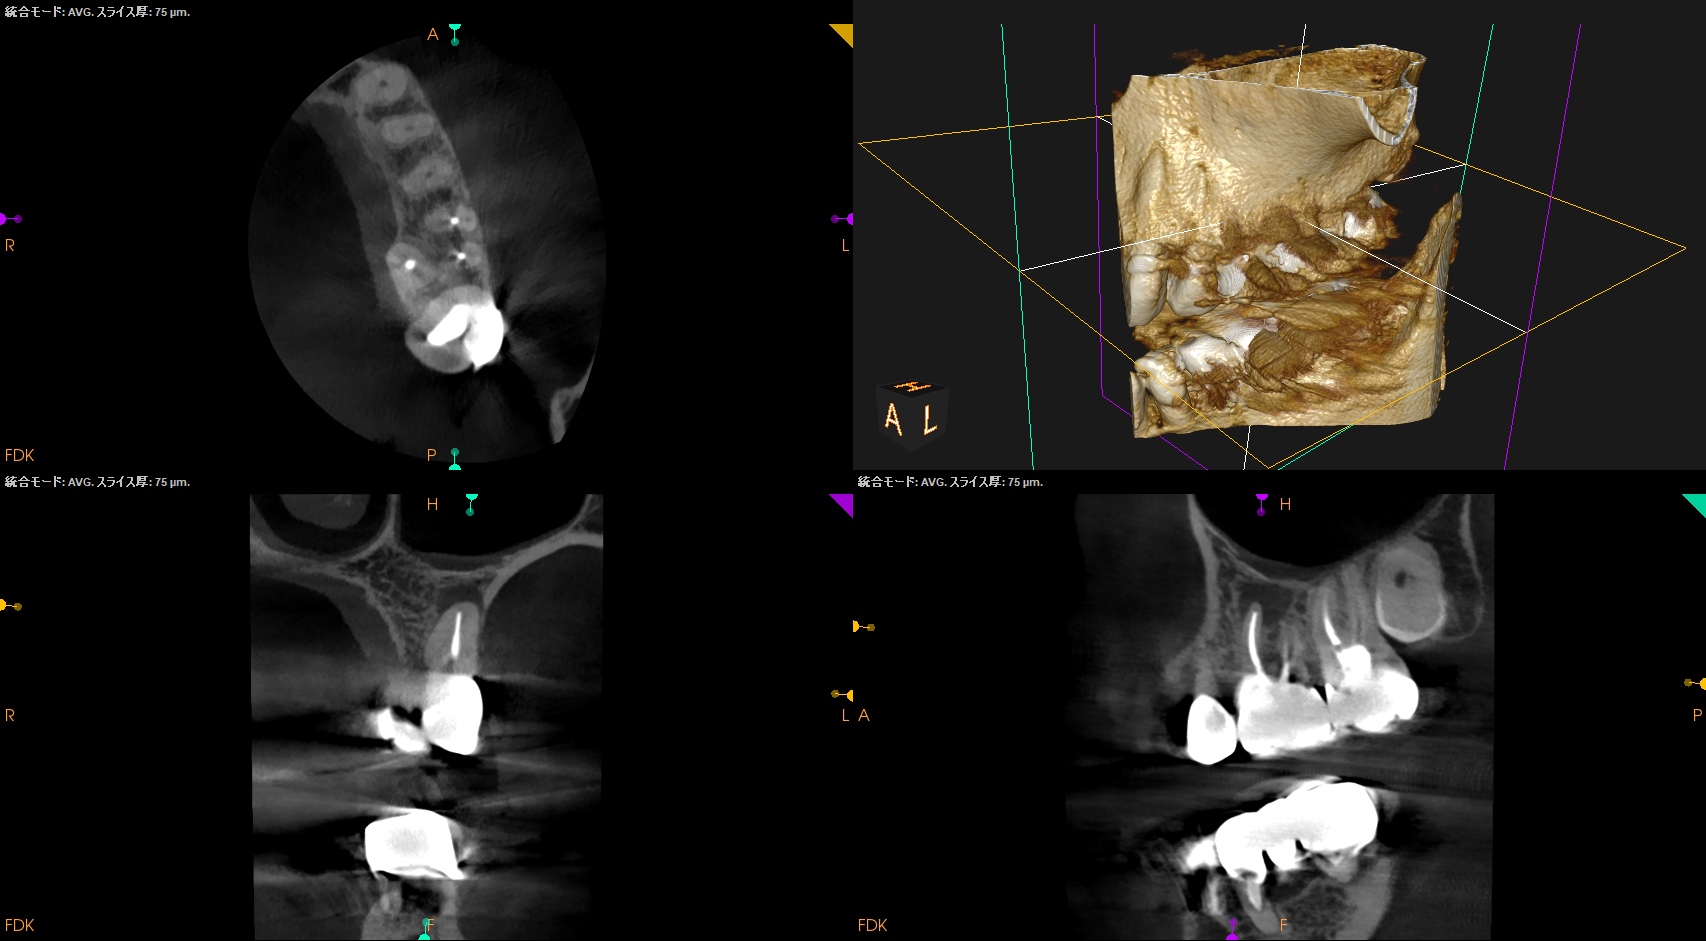

MBに大きな病変がある。DB,Pには病変はない。

これが検査での圧痛の原因だろう。

またすでに必要十分に拡大形成がなされていること,

MBの中央にGutta Percha Pointがあることから、MB2はなくMB1のみの処置でいいとわかるところもCBCTの強みである。

さておき、この問題を解決するには再根管治療でなく歯根端切除術であるということがわかる。

その際は、

クラウンのマージンより8.5mmの位置にMBのApexがあり3mm切断するには頬舌的距離が4.6mm必要で、MB2もないというまさにこの歯は奥歯だが、

事実上、上顎前歯のApicoectomy

と言える。